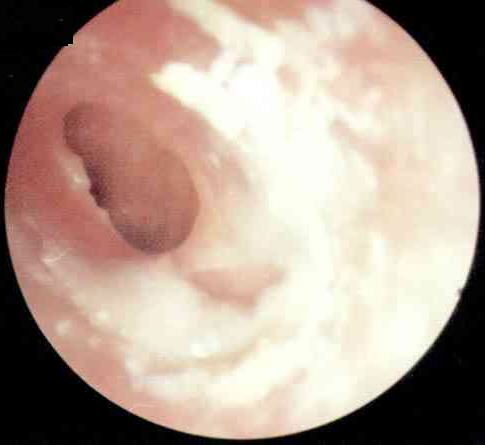

中耳炎病理图

西安新城中大耳鼻喉医院耳科张全安教授介绍,对于耳朵流脓,许多人都认为没什么了不起,是小毛病。但事实上,由于人的耳部与头颅内的脑膜很接近,中耳若感染发炎,可以通过血液循环或是通过内耳直接扩展到颅内,而引起颅内的并发症,严重时可以危及患者的生命安全。经过检查发现,刘先生属于化脓性中耳炎,病灶已侵犯到脑部造成脑脓肿从而导致头部剧烈疼痛,这个时候如果脓肿破裂则随时有生命危险。随后冯亮医生为他实施““全安”系统疗法”,有效解除了隐患。